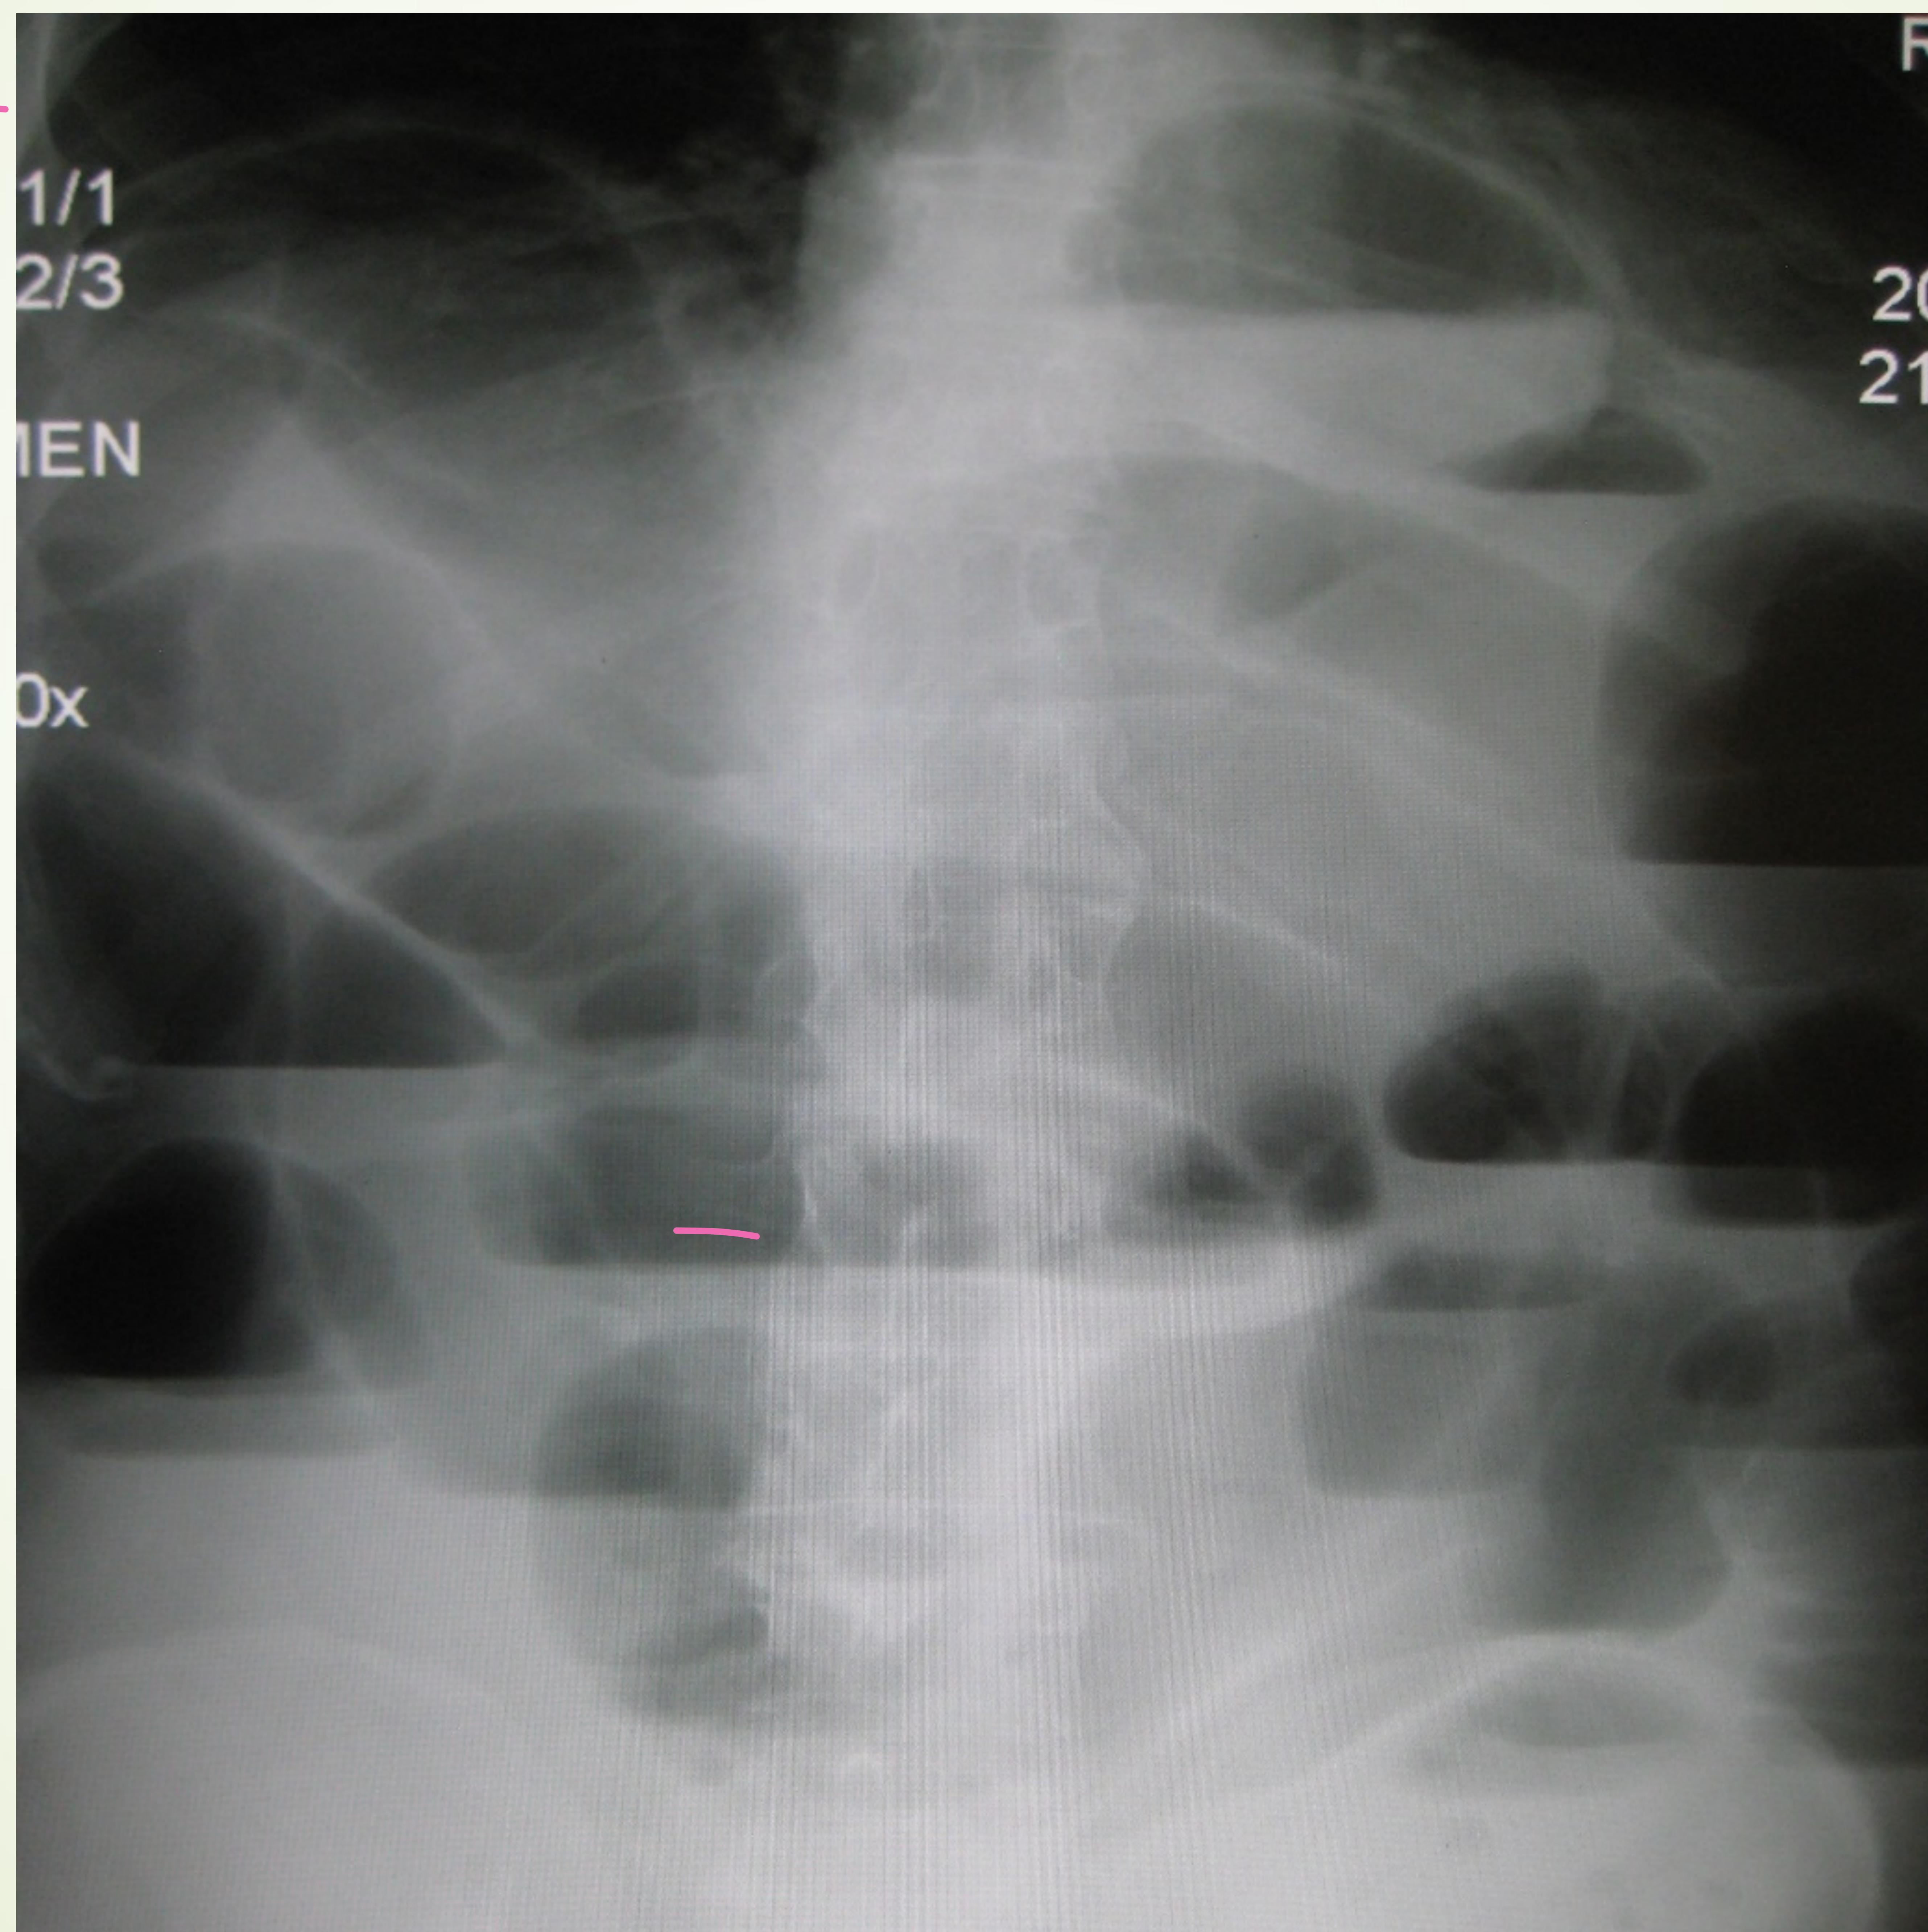

Upright abdominal X-ray showing multiple air-fluid levels.

- Imaging:

- Upright/flat abdominal X‑ray + chest X‑ray → look for air‑fluid levels, dilated loops, paucity of gas distal to obstruction.

- CT scan (gold‑standard): confirms obstruction, identifies cause, distinguishes partial vs. complete.

- Point‑of‑care ultrasound (POCUS) can aid early detection:

- Dilated loops > 2.5 cm

- “Tanga” sign (hyperactive to‑fro peristalsis)

- Wall thickening, reduced peristalsis